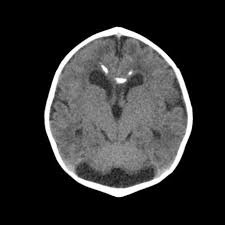

In this study, the data is sourced from Kaggle [7]. In this dataset, there are four subsets for training and testing, which are glioma, meningioma, no tumor, and pituitary. This study will focus on identifying meningioma, so the images in the ‘meningioma’ fold and ‘no tumor’ fold are used. In these two folds, there are a total of 2934 gray-scale images with different sizes. Some sample images can be found in Figure 1.

Figure 1. The sample images of the collected dataset (Left one is no tumor) [7].

In terms of the data preprocessing, this study converted all the images to RGB format and resize all the images to 256 × 256 for the DCGAN model and 512 × 512 for the CNN model. The study also does the normalization to the images.